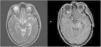

Los ganglioglioma son tumores bien diferenciados, de crecimiento lento, compuestos por una mezcla de células ganglionares maduras y gliales. La mayoría son de gradoI de la OMS. Aparecen predominantemente en niños y adultos jóvenes. La mayoría se localizan a nivel del lóbulo temporal, y la sintomatología más frecuente son las crisis epilépticas de difícil control farmacológico. En general tienen buen pronóstico tras la resección quirúrgica. La variante anaplásica, considerada gradoIII de la OMS, presenta mayor agresividad clínica y radiológica. La diseminación leptomeníngea es excepcional en estos tipos de tumores, pero cuando es diagnosticada presenta un curso rápidamente progresivo y fatal para el paciente.

Gangliogliomas are well-differentiated, slow-growing tumors. The majority are gradeI of WHO. It appears predominantly in children and young adults. Most are located at the temporal lobe, and as symptomatology more frequent epileptic seizures of difficult pharmacological control. In general, they have a good prognosis after surgical resection. The anaplasic variant, considered to be gradeIII of the WHO, presents greater clinical and radiological aggressiveness. Leptomeningeal dissemination is exceptional in these types of tumors, but when diagnosed it presents a rapidly progressive and fatal course for the patient.